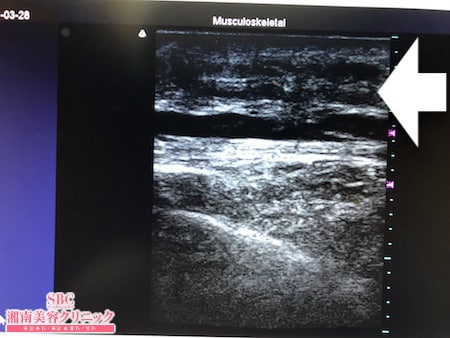

No.238059【脂肪吸引】【動画あり】湘南美容外科脂肪吸引最高責任者である竹田先生による脂肪吸引のフォトギャラリー!静岡県からご来院!何をやっても落ちない背中の皮下脂肪を脂肪吸引で根こそぐ!術中3Dタッチビュー・左ブラ下

その術中の変化を見ていただきましょう、。